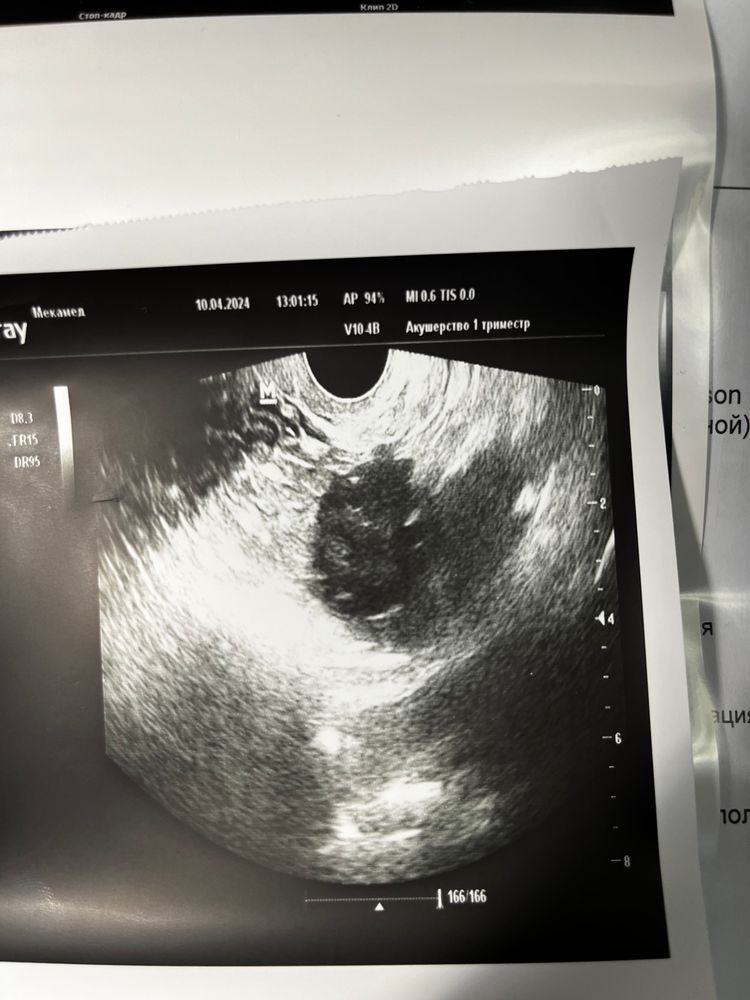

Это 21 дц с фолликулами до 10 шт в двух яичника Изображение ИзображениеА это 31 дц, где в девлм один а правый пустой Изображение

Анечка, а не рассмотрели ли вы там где пустой яичник, фоллики? Я увеличила и помоему там чтото есть🤔